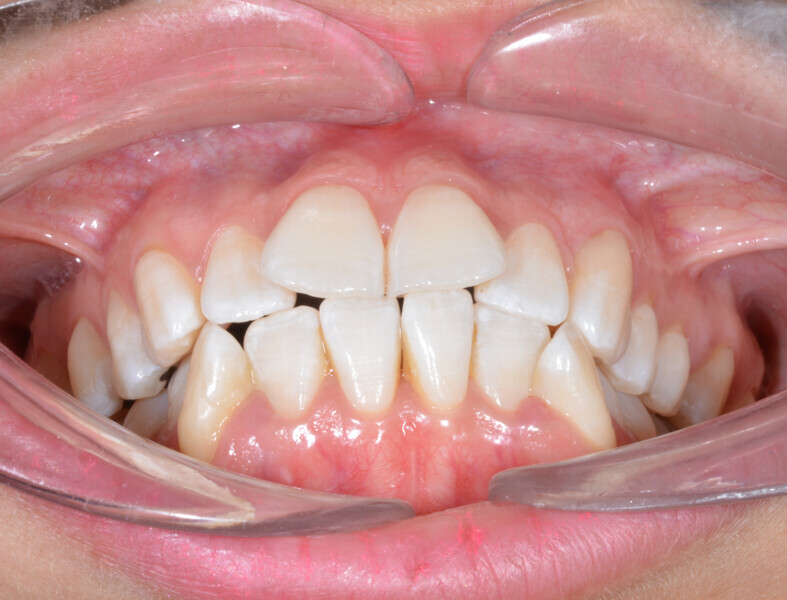

A 35-year-old female patient presented with crowding, muscle and joint pain, and headaches upon awakening. Examination found a skeletal Class I with crowding and bimaxillary protrusion. Facial examination showed a convex profile with protruded lips and a square face shape, intensified on smiling (Figs. 1–4). She reported bruxism, and bilateral masseteric hypertrophy was observed, but there was no alteration of the temporomandibular joints.

Before the aligner treatment began, the maxillary and mandibular second premolars were extracted to create space. With orthodontic treatment, distalisation of the anterior teeth was achieved by employing maximum mandibular anchorage and moderate maxillary anchorage (Figs. 5–7). At the end of the treatment, a stable bilateral Class I occlusion had been achieved, as well as normal inclination and retrusion of the anterior teeth, consequently improving the profile (Figs. 8–10).